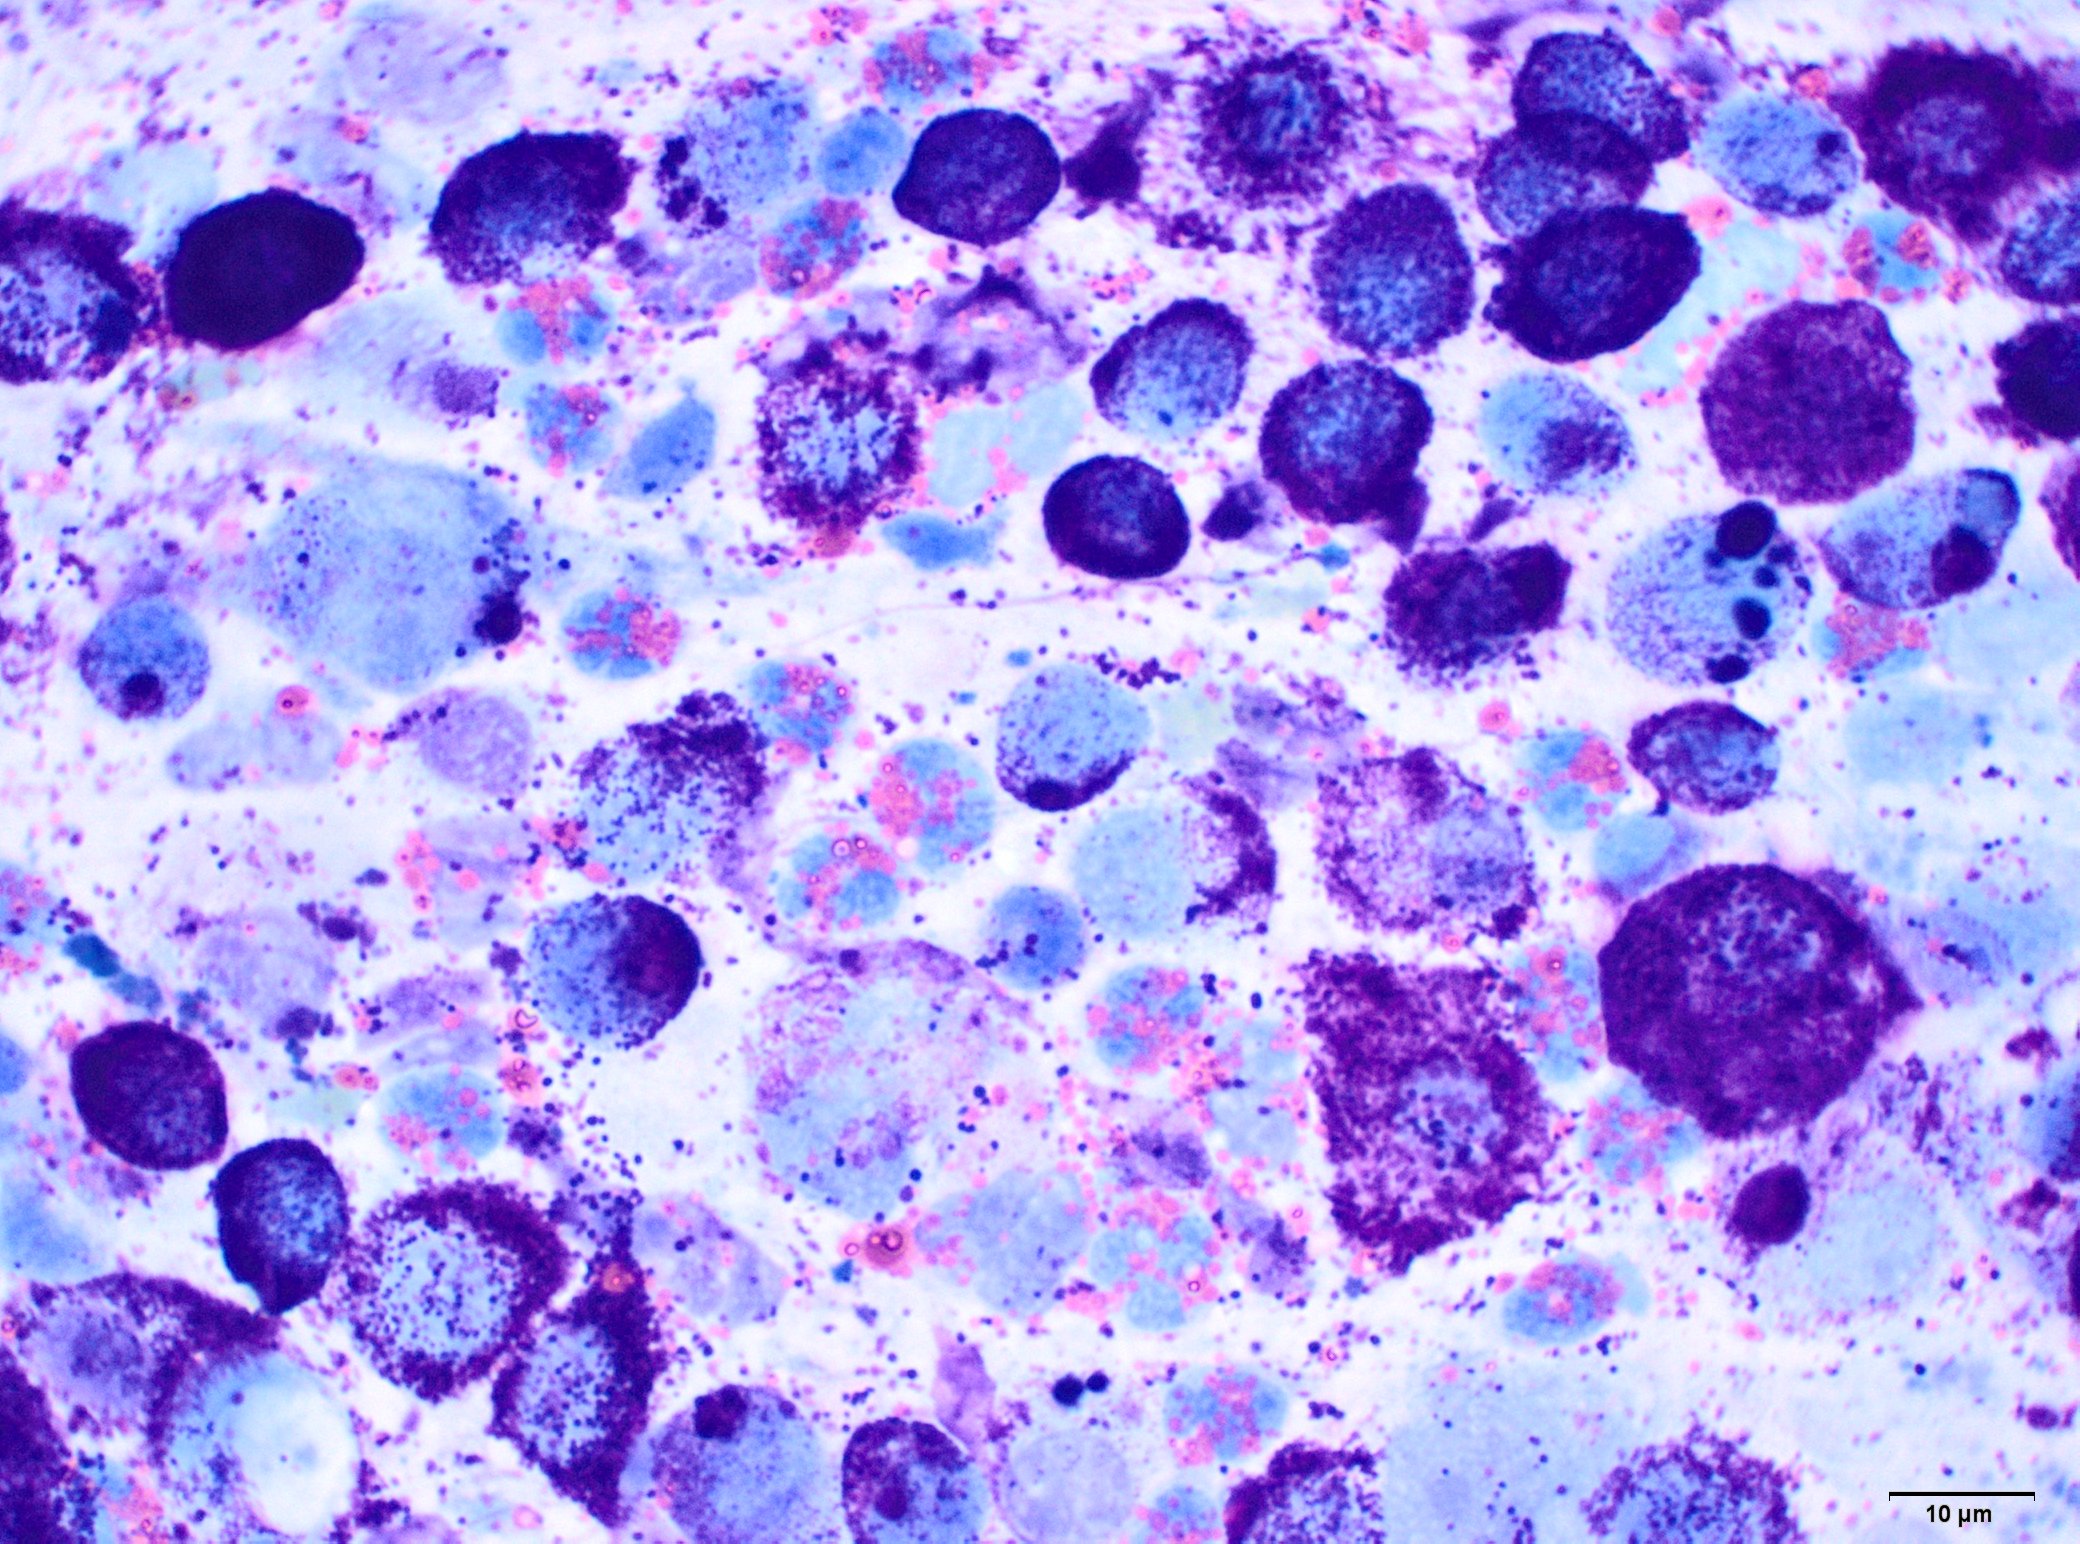

1) Le mastocytome est une tumeur à cellules rondes qui se reconnaît en cytologie par ses granules mauves caractéristiques.

2) Ces granules contiennent de l’histamine, ce qui explique l’aspect fluctuant de la masse : quand les mastocytes dégranulent (choc sur la masse par exemple), la libération d’histamine entraîne de l’œdème qui se résorbe ensuite.

3) Le mastocytome est souvent accompagné d’une infiltration éosinophilique, et parfois de fibroblastes et de collagène.

4) Les granules peuvent ne pas se colorer avec les kits de coloration rapide type hemacolor® ou diff-quick® avec potentielle erreur diagnostique à la clé. Préférez une coloration de May-Grunwald-Giemsa ou au bleu de toluidine quand un mastocytome est suspecté.

10) Mastocytémie (présence de mastocytes dans le sang) n’est pas synonyme de tumeur mastocytaire. C’est particulièrement vrai chez le chien chez qui plus de 50% des mastocytémies ne sont PAS liées à la présence d’un néoplasme mastocytaire. Néanmoins, en cas de mastocytémie, surtout si elle est massive comme dans le cas ci-dessous, la recherche d'une tumeur mastocytaire reste indiquée.